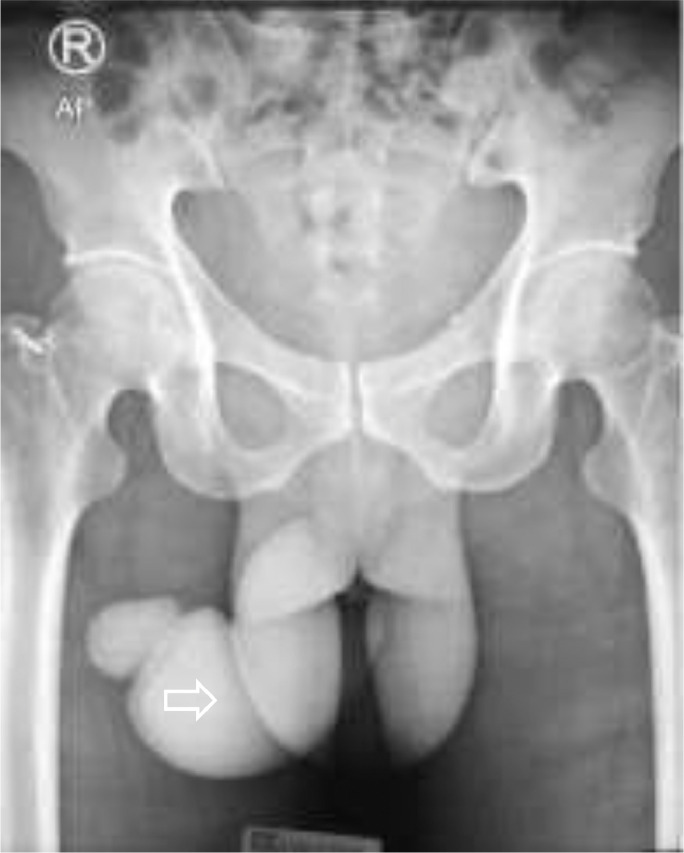

Fig. 2.

A plain abdominal radiograph showed soft tissue swelling in the penile region, with no diastasis pubic symphysis and opaque shadow in the urinary tract.